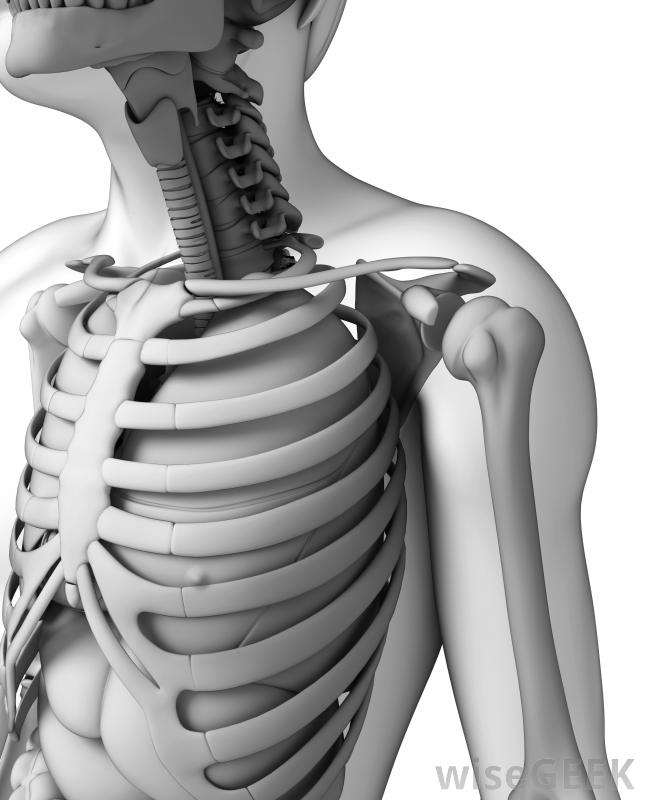

胸廓成形術包括縮短胸部特定部位的肋骨。對于脊柱側凸患者來說,這是一種相當常見的手術,因為它可以使脊柱側凸引起的肋骨隆起變小,也不那么嚴重。通常,病人在完成脊柱側凸矯正手術后,將進行胸腔成形術。胸廓成形術也可用于...

胸廓成形術包括縮短胸部特定部位的肋骨。對于脊柱側凸患者來說,這是一種相當常見的手術,因為它可以使脊柱側凸引起的肋骨隆起變小,也不那么嚴重。通常,病人在完成脊柱側凸矯正手術后,將進行胸腔成形術。胸廓成形術也可用于治療肺部疾病。例如,如果部分胸腔因結核、分枝桿菌或其他肺后疾病而感染,該手術可能是一種挽救生命的選擇胸廓成形術是脊柱側凸患者的常用治療方法,胸廓成形術可以減少由肋骨隆起引起的外部畸形,從而改善患者的整體外觀。此外,肋骨隆起可能相當疼痛,因此移除它可以減少或減輕與此相關的疼痛。例如,如果患者倚靠椅背時感到不適,去除肋骨隆起有助于降低不適程度。胸廓成形術包括縮短某些肋骨一般情況下,醫生會和病人討論胸廓成形術的部位,因為肋骨會縮短以減輕疼痛和減輕肋骨隆起,所以每個病人的情況都會被分析和考慮對于脊柱側凸的病例,肋骨的切除量取決于脊柱的曲線、駝峰的嚴重程度和大小。患者在完成脊柱側凸矯正手術后通常會進行胸腔成形術令人驚訝的是,在胸腔成形術完成后的兩到四個月內,肋骨或肋骨會重新生長并產生一個或多個新的肋骨。新的肋骨將與之前的肋骨一樣堅固,一旦愈合過程完成。不幸的是,如果脊柱彎曲繼續惡化,肋骨隆起可能會復發。因此,治療脊柱側凸非常重要,同時去除肋骨隆胸術后,大多數病人都戴一個支架來保護胸腔不受肋骨的傷害。這樣做可以防止肋骨摩擦胸腔內部器官,并減少胸腔積液的幾率,這就需要胸腔插管。基本上,雖然支架沒有什么作用,但它可以減少立即發生并發癥的幾率為了提高手術的效果。此外,無保護的胸壁在日常活動中幾乎沒有危險。當然,如果發生外傷,它可能會損壞胸壁。一個決定繼續前進的患者隨著胸廓成形術的進行,預計要在醫院呆四到八天。此外,完全康復可能需要幾個月的時間在進行這項手術之前,與一位聲譽良好的外科醫生討論所有問題和解決任何問題是很重要的。胸腔成形術可用于治療肺結核和其他肺部疾病。